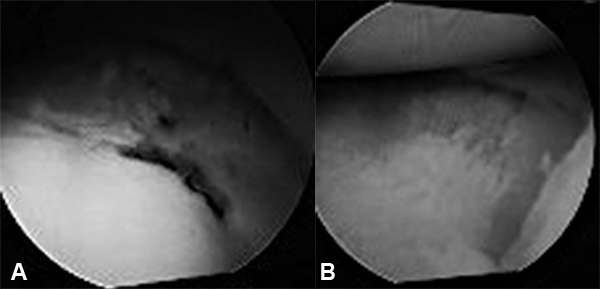

la rodilla), lo que permitió el drenaje del hematoma intraarticular, remover cuerpos libres, inspeccionar la superficie articular y diagnosticar lesiones meniscales o ligamentarias concomitantes (fig. 8).

Figura 10: Izquierda: Depresión Derecha: defecto reducido a nivel meniscal.

La visión artroscópica permite controlar bajo visión directa la reducción de la fractura, limpiar la hemartrosis, extraer pequeños fragmentos osteocondrales y valorar y tratar las lesiones asociadas factibles de ser resueltas con este método, evitando artrotomías o grandes abordajes, al mismo tiempo que permite un mejor postoperatorio inmediato y la rápida rehabilitación del paciente.